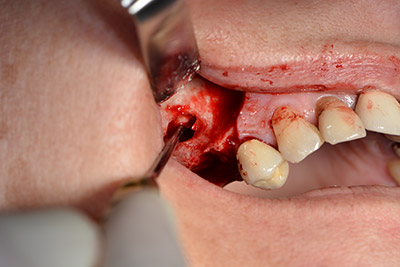

The classic incision (crestal, buccal relief) and the preparation of the mucoperiosteal flap enabled a good overview.

Sky implants (bredent) were used this case. The surgical protocol of these, specify pilot drilling at about 1200 rpm (Fig. 9).